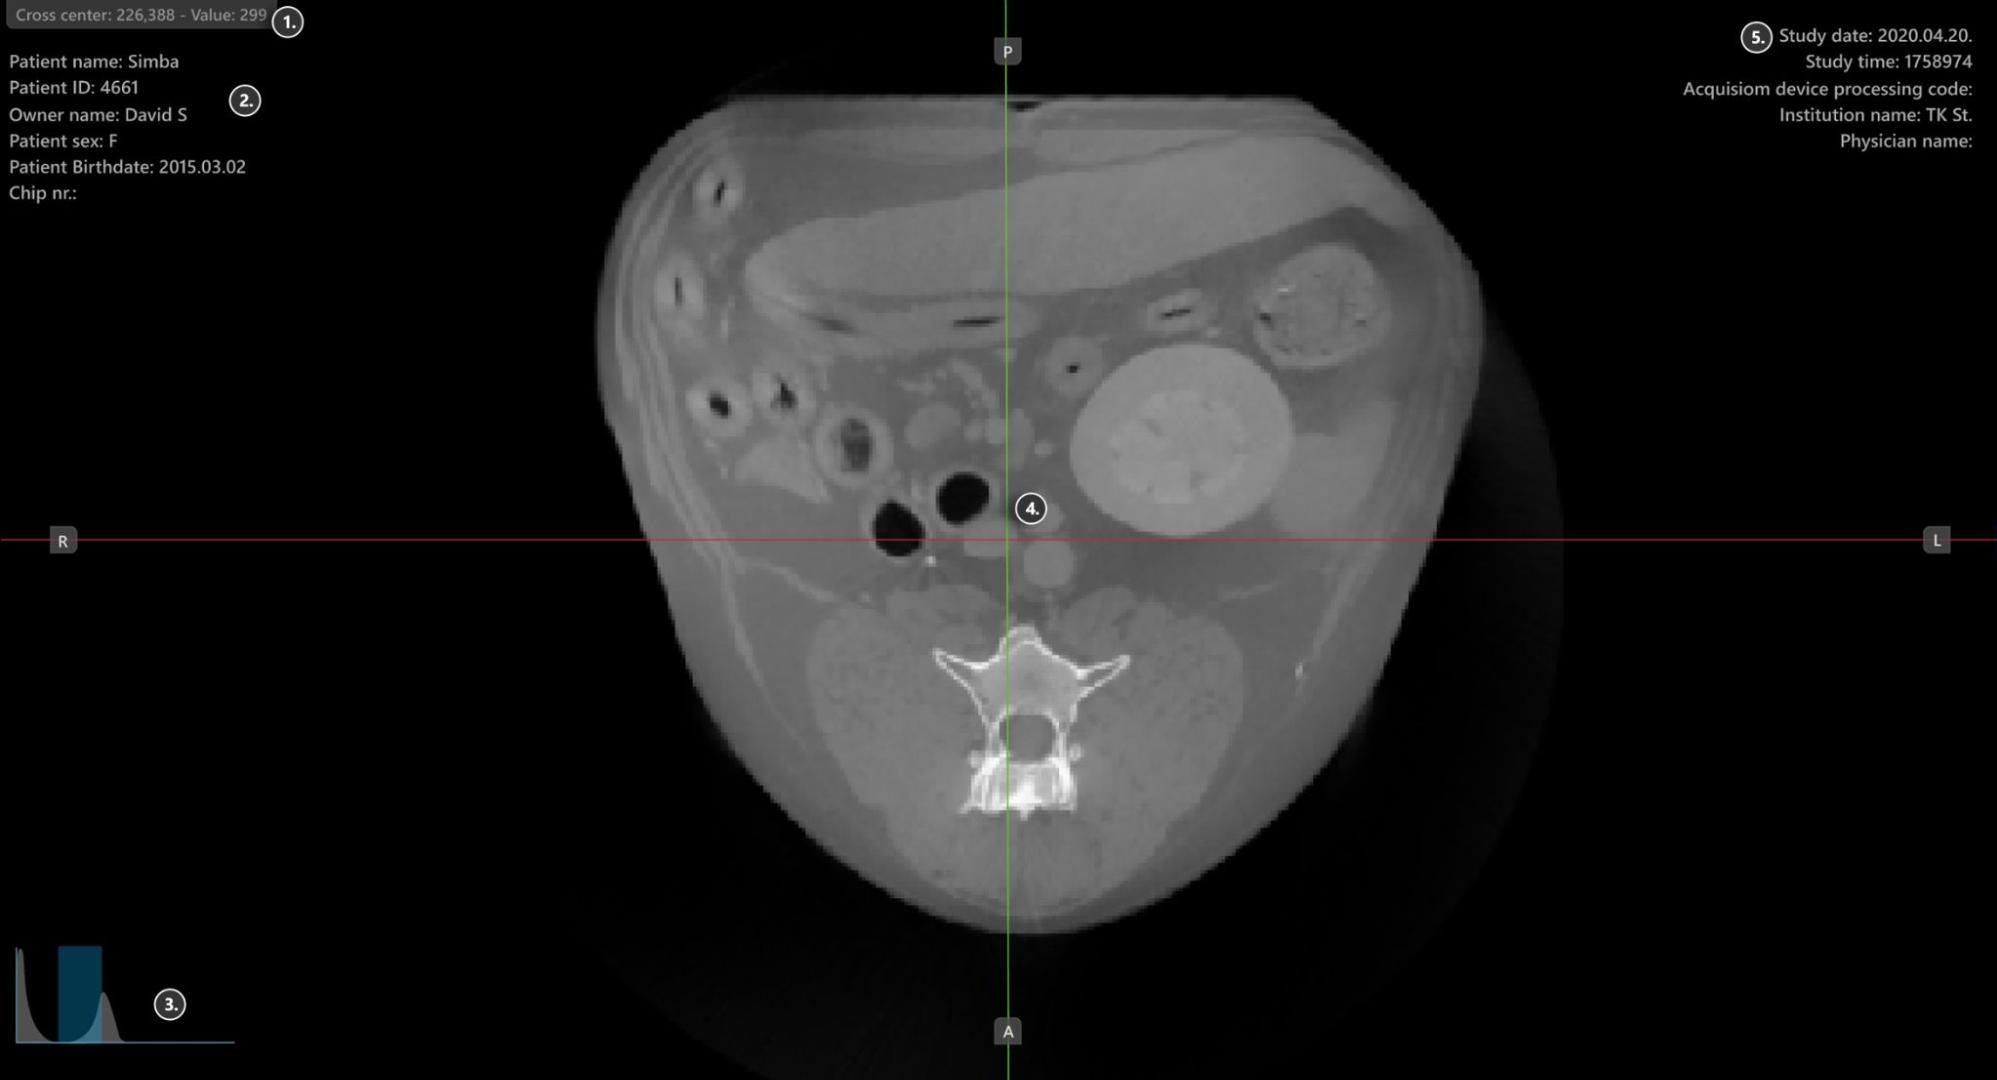

Viewer Area

../_images/image39.jpg

1. HU (Hounsfield Unit) pixel value

2. Patient information

3. Windowing histogram tool

4. Slicers

5. Study information